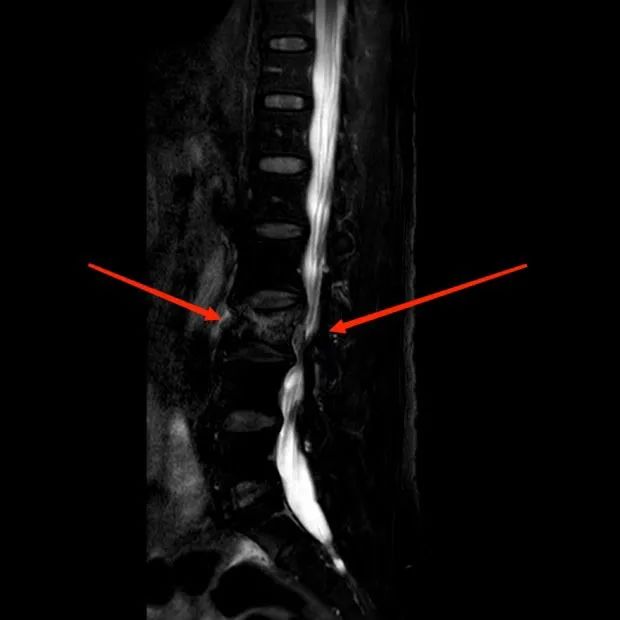

骨质疏松性脊柱压缩骨折是一种高发的骨质疏松骨折,好发于绝经后妇女及老年男性,国家骨质疏松基金会在2013年报道全球每3秒就会出现1例骨质疏松骨折,约50%的女性和20%的男性在50岁以后会出现骨质疏松骨折,而椎体骨折又是是骨质疏松骨折中发病率最高的,会严重降低患者的预期寿命,长期卧床的致死率、致残率极高。 脊柱由于承重着“一身之重”,其疼痛常会至人卧床不起,大部分的骨质疏松性脊柱压缩骨折都都发生在脊柱的胸腰段,这和脊柱的力学结构密切相关。骨质疏松性脊柱压缩骨折可能是由轻微暴力外伤诱发,甚至没有明显的外伤史都可能会出现,老年人的驼背、身高降低与此密切相关。部分严重的骨质疏松性脊柱压缩骨折和严重脊柱畸形甚至会导致神经损伤,值得我高度重视! 影像学检查中X线片具有重要意义,但早期的骨质疏松性脊柱压缩骨折X线片由于椎体高度丢失不明显,常会导致漏诊,延误病情,导致病情加重。磁共振是诊断骨质疏松性脊柱压缩骨折急慢性的重要手段,通过磁共振可以辅助骨质疏松性脊柱压缩骨折的诊疗决策。 治疗中,保守治疗和手术治疗都是需要权衡的,缓解疼痛、使用支具(腰托或胸腰骶支具)以及行走辅助工具是必不可少。卧床制动是最为基础和重要的治疗,随意的起立活动会导致骨折的椎体随着屈曲应力和轴向压缩的力量愈发的形变,引起更为严重的后果。 经皮穿刺椎体成形术是治疗骨质疏松性脊柱压缩骨折的革命性手段,通过向病变椎体内注入骨水泥或人工骨达到强化椎体的目的。20世纪90年代以来其微创、起效迅速的特性,极大的改善了患者的生活质量。同时,一些严重的、侵犯椎管的骨质疏松性脊柱压缩性骨折需要行椎管减压、椎弓根钉内固定的手术治疗。 磁共振提示第三腰椎的新型压缩性骨折 王阿姨通过磁共振明确了是第三腰椎的骨折,综合决策后在岳阳医院骨伤中心完成了经皮穿刺椎体成形术的治疗,术后疼痛即刻得到明显缓解,次日便绑着腰托下地行走了。经此,医生告诉王阿姨要更加重视自己的骨质疏松症,并且要避免跌坐,否则有可能会再此骨折。 经皮穿刺椎体成形术后的X线影像 参考文献: 《骨质疏松性骨折诊疗指南》 中华医学会骨科学分会骨质疏松学组 作者:上海中医药大学附属岳阳中西医结合医院 骨伤中心 冯圣一 李勃 上海市虹口区曲阳路街道社区卫生服务中心 针伤科 陆文婷 延伸阅读